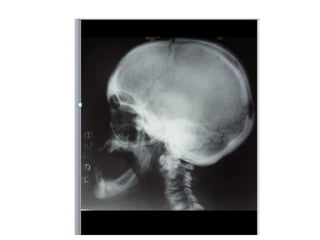

Lateral radiograph of the skull reveals diffuse thickening of the calvarium, most

significant in the region of the occiput. The partially visualized upper cervical

vertebrae and maxilla are also dense and thickened.